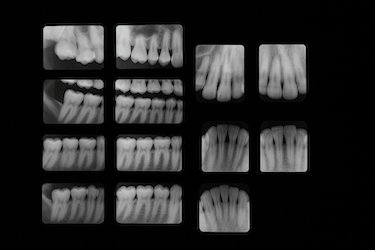

El doctor será el encargado de analizar tu caso mediante un examen, haciendo especial hincapié en encías y huesos, y con diversas pruebas. Una vez que tenga claro el diagnóstico, te recomendará la mejor opción de tratamiento atendiendo a tus necesidades.

Diagnóstico completo con radiografías y periodontograma para medir bolsas y pérdida ósea. Te damos un plan de tratamiento personalizado en la misma visita.